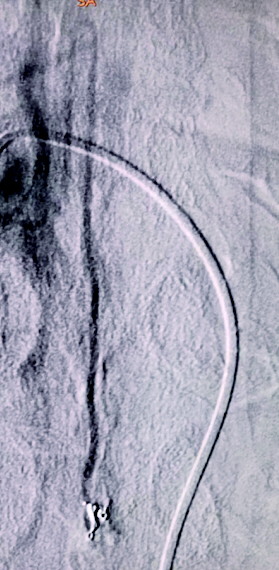

充分做好术前准备,术中微导管置入供血动脉,给予超选造影发现,瘘口距离下方的脊髓前动脉很近,只有2-3mm的距离,术中必须保护好脊髓前动脉,脊髓前动脉如果发生闭塞就有发生截瘫的危险。

图A为术前造影的正位图像,主供血为脊髓前动脉,引流静脉的起始部形成一个静脉球,远端呈迂曲状;图B为微导管到位后的超选造影,脊髓前动脉不显影(已越过);图C为栓塞结束后的造影,主供血的血流明显瘀滞,瘘口闭塞,下方的脊髓前动脉仍显影。